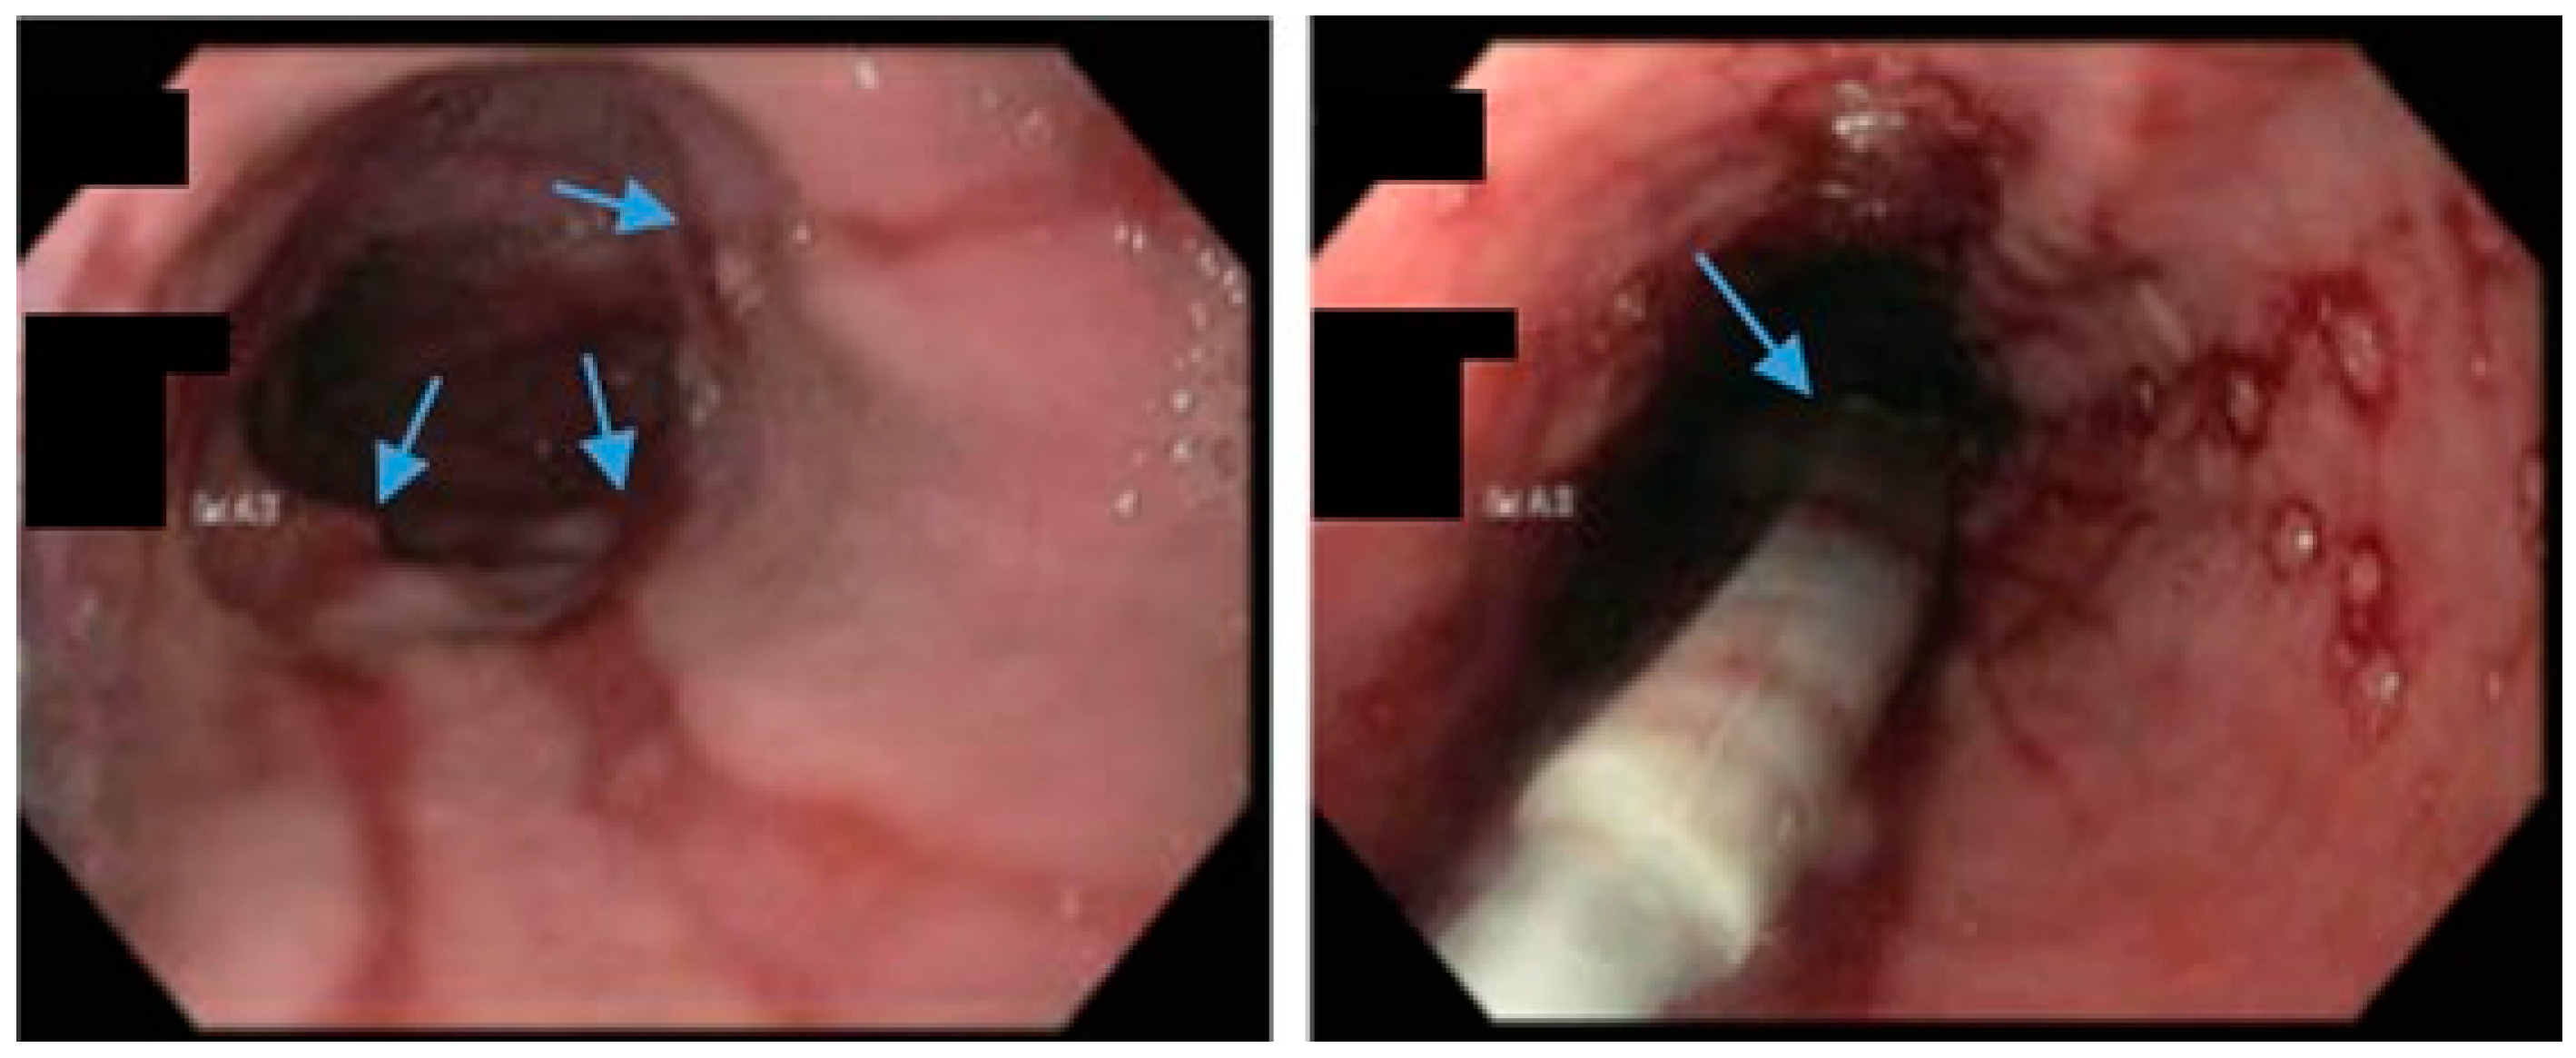

Figure 5.

Upper endoscopy demonstrates Los Angeles Grade C esophagitis in a patient following sleeve gastrectomy (arrows, left). A Bravo™ capsule was placed endoscopically for pH monitoring (Medtronic, Minneapolis, Minnesota, USA) (arrow, right).

Due to the association of SG with an increased risk of GERD, it is paramount for clinicians to discuss the risk of exacerbation of pre-existing GERD and the development of new-onset GERD during the shared decision-making process with potential candidates for SG (Figure 5). Data regarding the long-term risk of PPI use and the risk of cardiovascular adverse events should be considered as they relate to the treatment of GERD post-SG.

An international expert panel on sleeve gastrectomy reported that 52.5% of general surgeons and 23.3% of bariatric surgeons considered GERD as a contraindication to SG [65]. According to a multi-society consensus statement, SG should not be performed as an antireflux procedure [66]. Data suggest that patients with a BMI > 35 and medically refractory GERD should be considered for RYGB rather than fundoplication due to the following: an increased risk of hiatal hernia and GERD recurrence with fundoplication in patients with BMI > 35, as well as an additional weight loss and metabolic benefit conferred by RYGB to address a myriad of comorbidities [66,67,68,69,70].